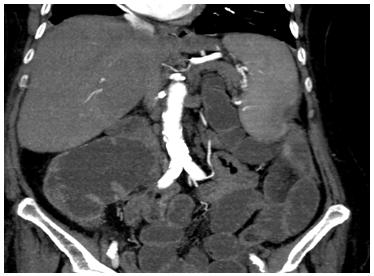

A 78-year-old female patient who was admitted to the emergency department with complaints of worsening abdominal pain, nausea, and vomiting for three days was considered as an acute abdomen. On physical examination, rebound and defense were found positive in the left upper quadrant. On auscultation, there was also hyperactive bowel sound. The patient with known ischemic heart disease and arrhythmia has no previous abdominal surgery. She had no infectious diseases like tuberculosis. The patient with mildly high leukocytosis and a C-reactive protein of 90 mg/L was prepared for an emergency operation. In her abdominal computed tomography (CT), acute mesenteric ischemia was suspected due to dilated ileal loops, diffuse air-fluid levels, and dilatation in the proximal colon Figure 1. However, any vascular event could not be detected at the CT screening. According to all these clinical information, the patient was prepared for an emergency operation. First of all, diagnostic laparoscopy was planned for the patient. Although it was tried with open technique, laparotomy was performed due to the inability to enter the abdomen. During exploration, many adhesions could be defined as the cocoon surrounding all organs, and free fluid was not seen in the abdomen Figure 2. Numerous bridotomy-bridectomies were performed. The closed perforation area was detected as a mass lesion at the splenic flexure and a left hemicolectomy had to be performed. The patient was discharged on the 5th postoperative day after intestinal function improved gradually. A 2-years follow-up period was performed and no recurrence was detected. In the pathological examination, ACS-related perforation was confirmed in the patient.

Figure 1 Dilated intestinal anses with the air-fluid level at the CT.